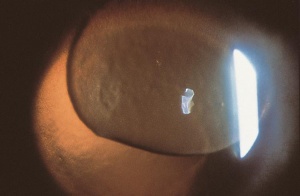

Traumatic lens injury may present as an acute, subacute, or late sequela of ocular trauma and is one of the major causes of acute or long-standing visual loss after injury to the eye. Cataracts and zonular dehiscence following blunt trauma are the result of coup (direct) and contrecoup (indirect) injury to the lens.[35] The resulting traumatic shockwave and equatorial expansion of the globe causes injury to both the anterior and posterior lens structures leading to capsular and zolunlar disruption and cataract which may be stable or progressive. Coup injury is also responsible for the imprint of pigment on the anterior lens capsule known as the Vossius Ring that is frequently seen in these cases. Penetrating trauma or intraocular foreign bodies can lacerate the anterior lens capsule, leading to focal cortical changes, or rapid lens opacification. The lens material that maybe released after both blunt and penetrating injury can lead to severe intraocular inflammation and elevation of intraocular pressure. [36]

Patients with traumatic cataract complain of decreased vision, glare and monocular diplopia. While a traumatic cataract may result immediately following the injury, it may also develop gradually over weeks, months or years. Some traumatic cataracts remain localized and stable, while others may progress to total lens opacification. The traumatic cataract is classically described as subcapsular and star-shaped, and is known as a Rosette Cataract. Other types of cataract, such as a mature white cataract can also be seen. Lens swelling and the integrity of the anterior and posterior capsule should be documented and, in the acute setting, the severity of lens-associated intraocular inflammation should be graded.